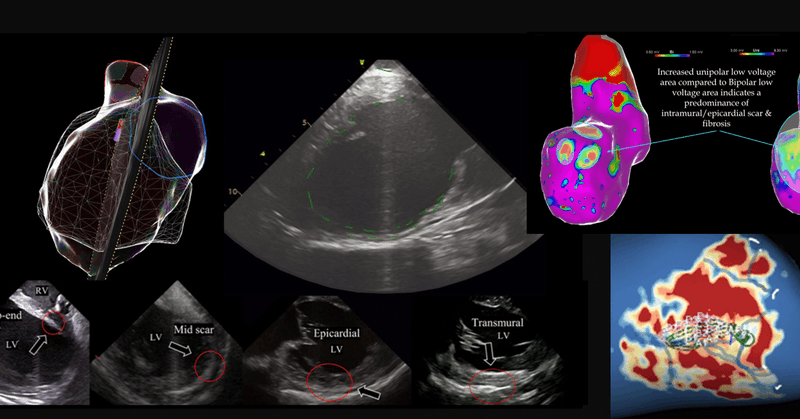

πŸš€New #BeatBoxBlog post! πŸš€ This week focuses on identifying intramural ventricular substrate! 1. Bipolar Vs Unipolar Voltage maps 2. ICE mapping 3. Cardiac MRI #epeeps #epfellows #foamed #meded #ecg #ablatevt #cardioed https://t.co/I3iN0zbq62